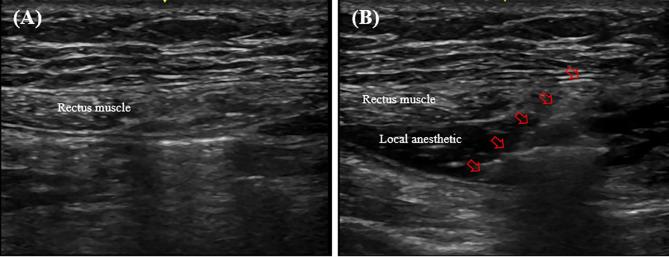

This prospective, randomized controlled trial included 72 donors undergoing elective hand-assisted living donor nephrectomy into two groups: propacetamol (n = 36) and nefopam (n = 36). Intraoperative RSB was performed in all enrolled donors. The primary outcome was the total volume of intravenous opioid-based patient-controlled analgesia (PCA) used on postoperative day 1 (POD 1). Additionally, the Numeric Rating Scale scores for flank (visceral) and umbilicus (parietal) pain at rest and during coughing were compared, and the Korean adaptation of the Quality of Recovery-15 Questionnaire (QoR-15 K) was evaluated on POD 1.

本前瞻性、随机对照试验纳入了 72 名接受择期手助活体供肾切除术的供者,分为丙帕他莫组(n=36)和奈福泮组(n=36)。所有入组的供者均行术中 RSB。主要结局是术后第一天(POD1)静脉内基于阿片类药物的患者自控镇痛(PCA)的总用量。此外,还比较了两组患者在静息和咳嗽时的肋部(内脏)和脐部(壁部)疼痛的数字评分量表(NRS)评分,并在 POD1 时评估了韩国版恢复质量 15 问卷(QoR-15 K)。